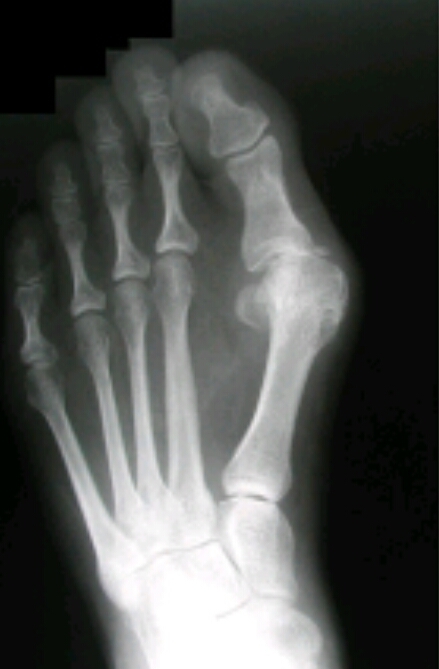

Name the feature. What disease does this represent?

hallux valgus

DJD

Name the feature. What disease is this associated with?

metatarsus varus

Name the feature. What disease does this correlate with?

(Inflammation, pain)

bunion